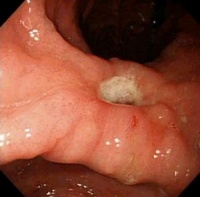

2.纤维十二指肠镜检查:除可发现憩室的开口外尚可了解憩室与十二指肠乳头的关系,为决定手术方案提供依据。